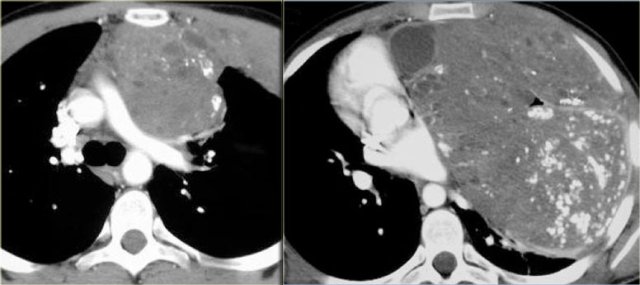

Neuroblastoma Neuroblastoma

On the MR-images the invasion of the vetebral canal is better seen (arrows).

Extramedullary hematopoiesis masses in the paraspinal area and adjacent to the sternum. Extramedullary hematopoiesis masses in the paraspinal area and adjacent to the sternum.

Extramedullary hematopoiesis

Extramedullary hematopoiesis accounts for less than 0.1 % of the lesions in the posterior mediastinum.

It is characterized by formation of blood elements outside of the bone marrow. It occurs with severe anemia.

On CT it is seen as a paravertebral mass and occurs with coarse bone trabeculation in the adjacent vertebra.